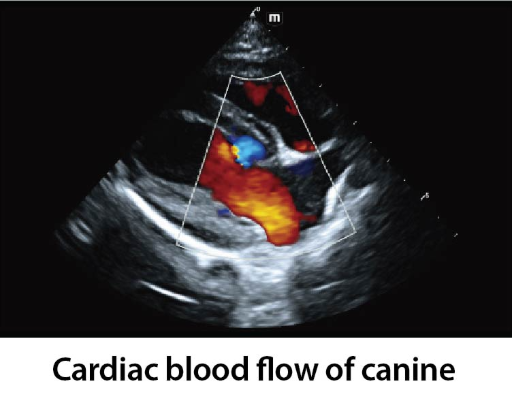

Клинични снимки

Clinical Images